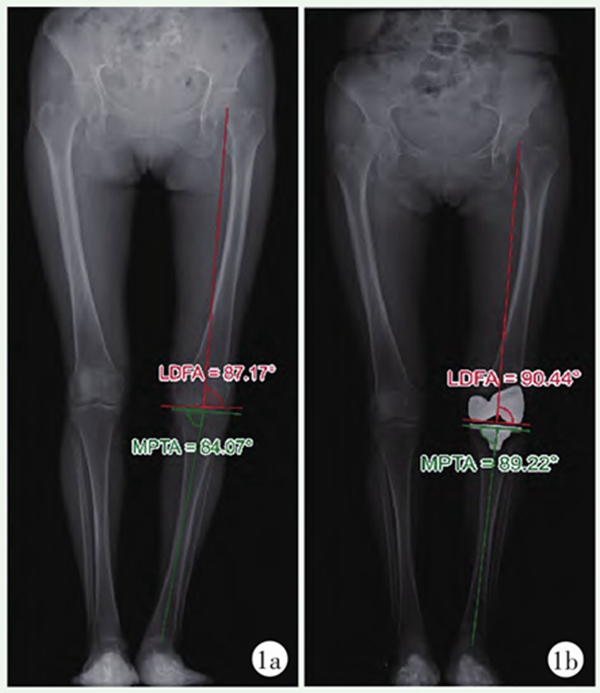

1973年,Freeman等提出垂直股骨胫骨机械轴截骨的概念,不久后,Insall等强调了膝关节置换术间隙平衡的重要性,自此,机械力学对线便成为膝关节置换的“金标准”。机械力学对线强调垂直于股骨及胫骨各自的机械轴进行截骨,由此得到一个中性对线的膝关节,关节内外侧间室的压力均匀分布,从而将假体磨损及松动的风险降至最低(图1)。偏离中性机械对线,可造成聚乙烯衬垫磨损加速、骨溶解及假体下沉的风险,从而影响假体的使用寿命。临床证据证明该技术能够保证良好的假体远期存活率和可接受的功能活动。此后人们逐渐形成共识:TKA术后下肢机械轴偏离值应控制在±3°范围内(即髋-膝-踝角应小于±3°),以防止中长期的假体失败风险。但越来越多的证据表明,该对线方法带来的患者术后满意度并不高。来自英格兰和威尔士国家联合登记处的数据表明,近20%的患者对自己术后功能不满意。然而,无论是使用技术辅助手段以提高置入物的精确度,还是新的置入物设计,都无法进一步提高患者的满意率。研究显示MA技术存在先天的局限性:它通过改变固有解剖结构、生理性韧带平衡和运动学特点来制造的非生理性膝关节,改变了软组织原本的张力、打破了原有的运动平衡,从而导致患者功能及症状的改善程度均不高。

图1 MA-TKA患者双下肢站立位全长X线片

1a:术前X线片;1b:术后X线片患者股骨及胫骨排列被矫正至90°中立位;LDFA:股骨远端外侧角;MPTA:胫骨近端内侧角